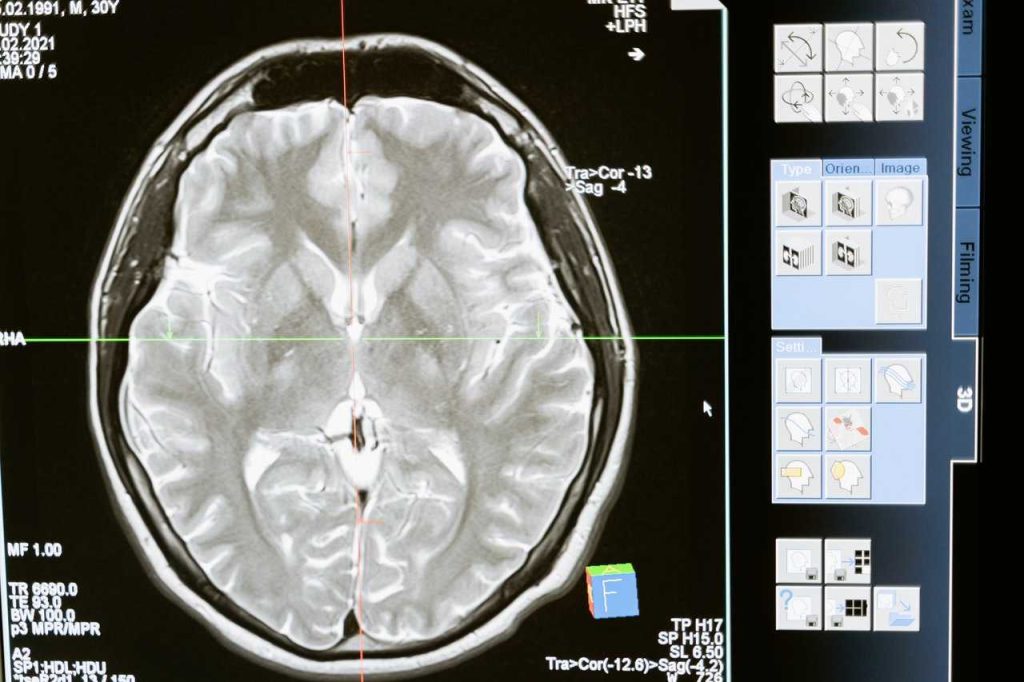

Adicción al azúcar: Cuando se ingiere dulce se activa un sistema de recompensa y la liberación de dopamina, un químico neurotransmisor.